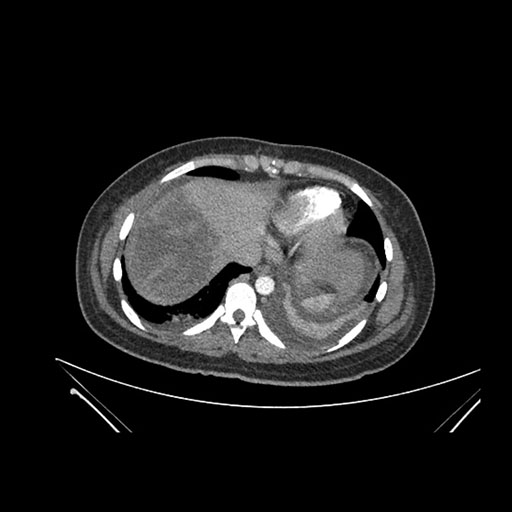

Imaging Analysis

Look through the patient's CT scan to identify any areas of concern for the necessary procedure.

Axial Venous

Based on initial findings, which issue(s) would you be most concerned about?